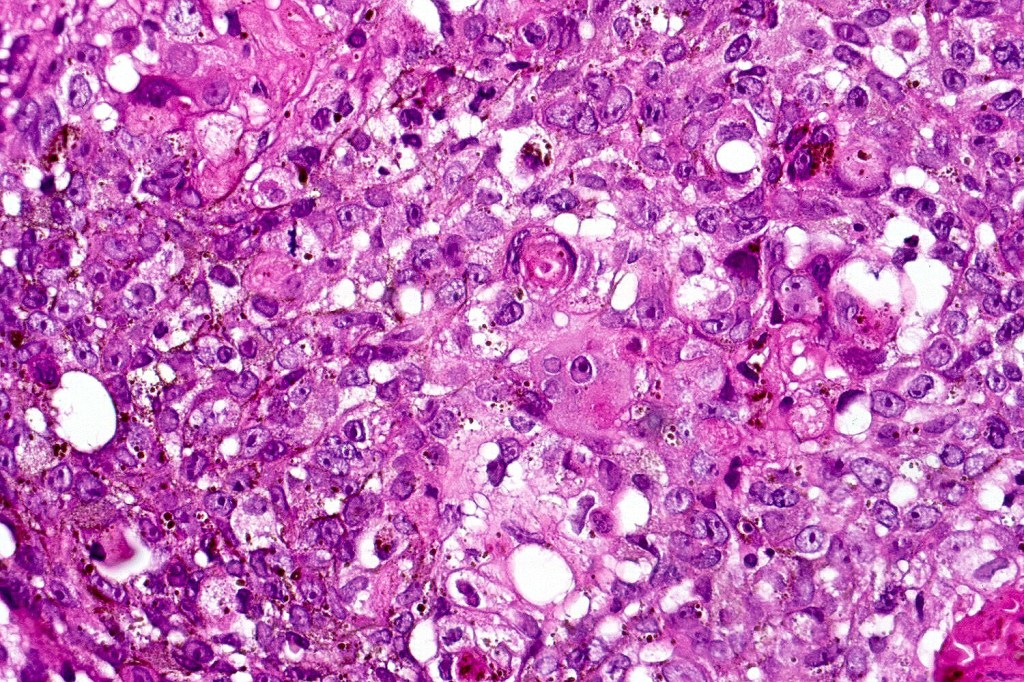

•Basaloid population with prominent nucleoli accompanied by supramatricial and ghost cells

•Variable pleomorphism

•Mitoses may be conspicuous

•Heavily pigmented dendritic +/- epithelioid melanocytes